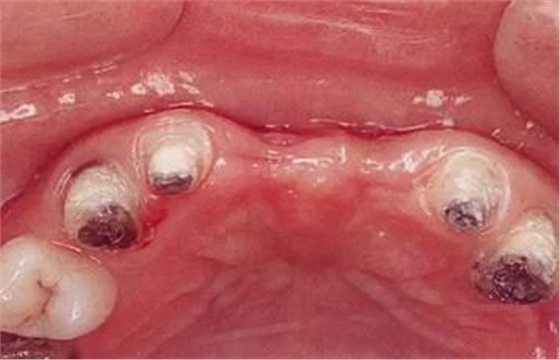

▲圖7-1

對(duì)上頜前牙進(jìn)行初期治療后的咬合面觀。右上2,3存在炎癥。